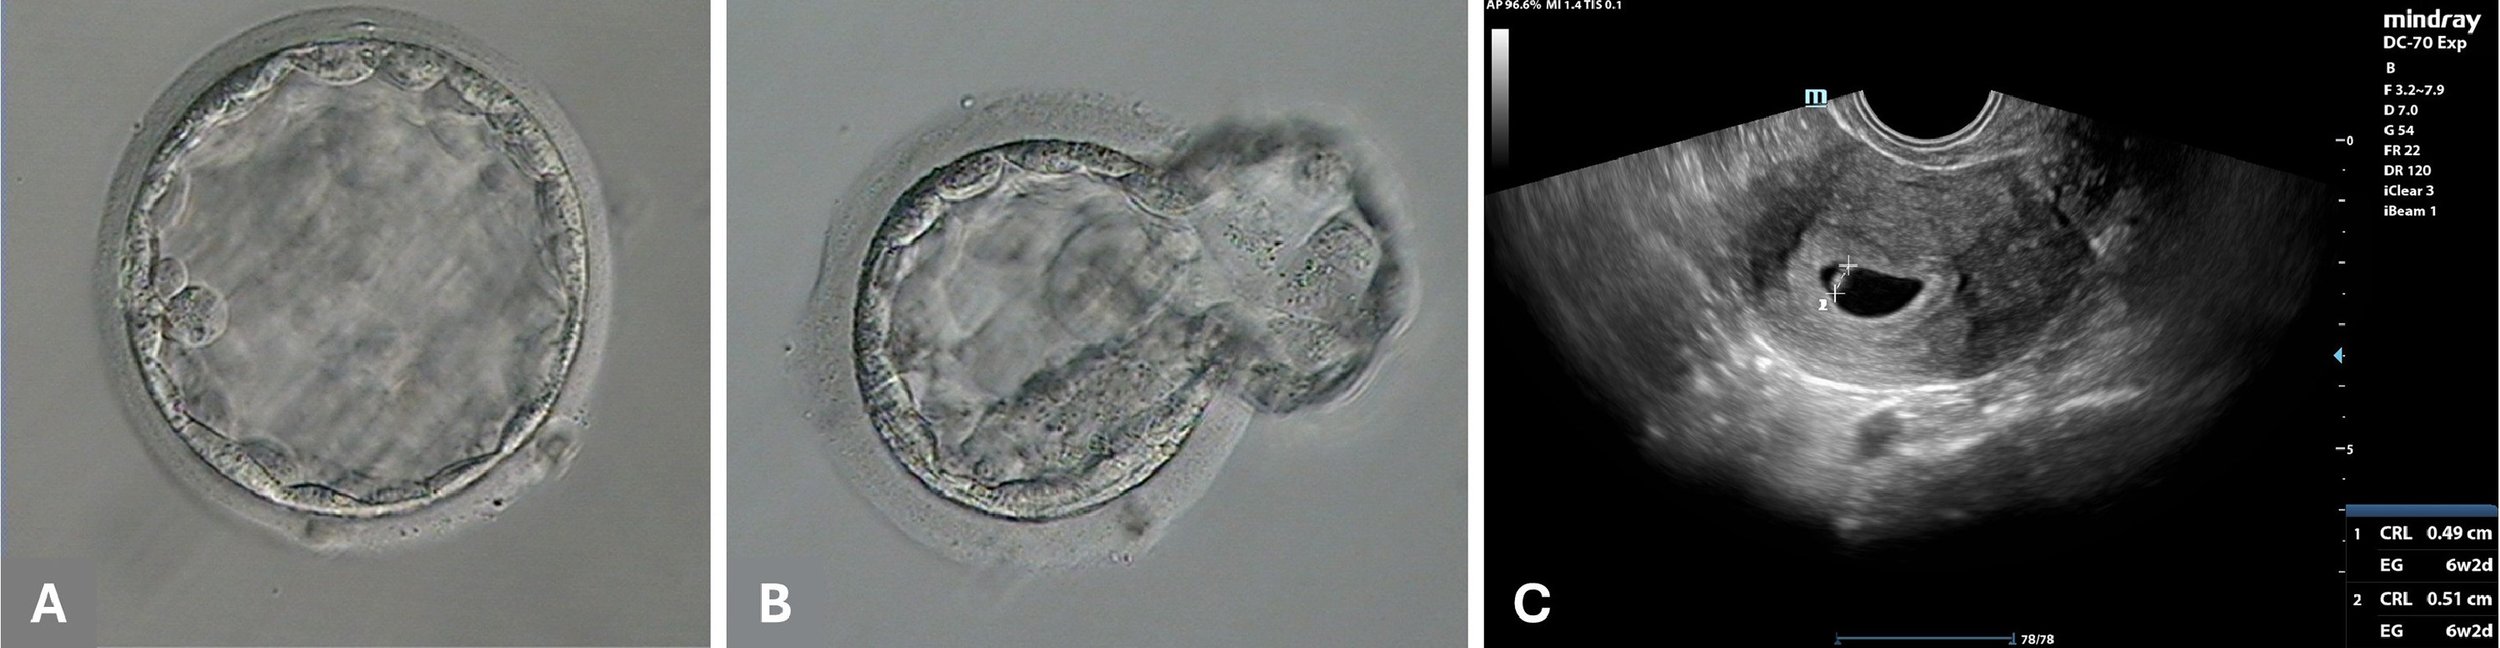

Fertilization and blastocyst formation rates were satisfactory, with four injected oocytes achieving normal fertilization in the remote ICSI group (80%, n = 4/5), compared with three oocytes in the control group where ICSI was performed manually using the standard protocol (100%, n = 3/3). Following embryo culture, two usable blastocysts were produced by remote ICSI and an additional two usable blastocysts were produced in the control group. All but one of the embryos were vitrified. ERICA AI was used to rank the embryos. A fresh embryo transfer with the remote ICSI blastocyst (Figure 2A) which had the highest ERICA ranking did not lead to pregnancy. However, a successive transfer with a vitrified-warmed remote ICSI blastocyst (Figure 2B) with the second highest ranking resulted in a blood β-HCG concentration of 61 mIU/ml on cycle day 25. The remote ICSI procedure for this blastocyst was conducted in Hudson, New York (USA), approximately 3700 km away from the gametes and IVF laboratory. An ultrasound scan performed in week 6 of pregnancy confirmed the presence of a single gestational sac with a fetal heartbeat (Figure 2C). The pregnancy continued uneventfully, with normal fetal growth. No complications were reported during delivery through elective caesarean section, which resulted in the delivery of a healthy male child at 38 weeks of gestation (weight 3.3 kg, height 50 cm, Apgar score 9). A further two blastocysts obtained in the control group remain cryopreserved at the time of writing.

Figure 2 Fresh transfer of a good-quality blastocyst produced by remote intracytoplasmic sperm injection (ICSI) (A) did not result in pregnancy. A cryopreserved blastocyst produced by remote ICSI re-expanded within 4 h after warming (B) resulted in a clinical pregnancy after assisted hatching and embryo transfer (C).